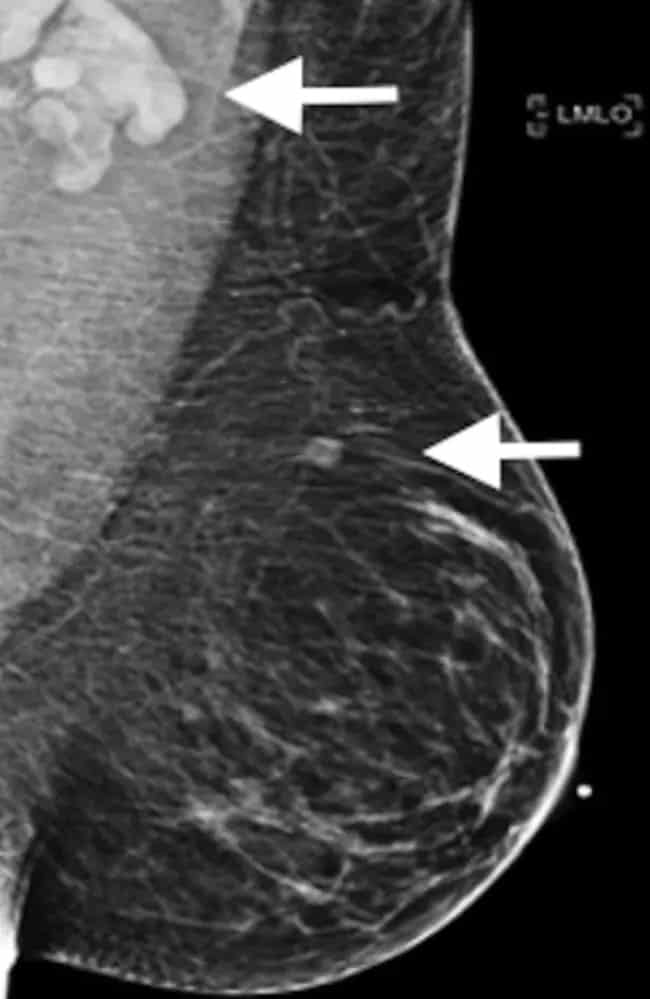

Cách hạch bạch huyết bị viêm sưng của một phụ nữ sau khi tiêm vắc xin Covid-19. Ảnh: Radiological Society of North America

Một nghiên cứu được công bố bởi Hiệp hội X-quang Bắc Mỹ, gần đây kết luận, nổi hạch sau tiêm vắc xin là một tác dụng phụ mà các bác sĩ lâm sàng, bệnh nhân và các nhà nghiên cứu ung thư cần lưu ý vì rất dễ nhầm lẫn nó thành cách triệu chứng của ung thư vú.